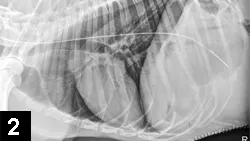

Figure 1. Ultrasound of the right upper quadrant of a dog’s abdomen showing changes often noted with pancreatitis (eg, thickened, hypoechoic pancreas [yellow arrow], surrounding hyperechoic mesentery [white arrow]).

• Ultrasonography (See Figure 1) remains one of the most common methods to diagnose pancreatitis.

• A skilled ultrasonographer can often identify characteristic ultrasonographic changes consistent with pancreatitis (eg, enlarged hypoechoic or mixed echogenic pancreas with surrounding hyperechoic mesenteric tissue, variable distention/functional obstruction of the biliary system, small amounts of free fluid in the abdomen consistent with focal peritonitis, thickened or corrugated appearance to the duodenum, intestinal ileus).

• A normal ultrasound does not rule out pancreatitis.